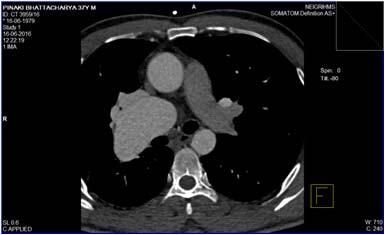

Echocardiogram was normal with normal pulmonary artery pressure except for absent right pulmonary artery. A chest radiograph (postero-anterior view) revealed dilated artery (?Main pulmonary) in the right hilum with alveolar infiltrates in right lung field. The right hemi diaphragm was elevated without any cardiac and mediastinal displacement (Fig 1). Computed tomography (CT) angiogram revealed the absence of the right main pulmonary artery. A focal vascular dilation was detected in right lung possibly representing an aneurysmatic formation or an arteriovenuous fistula (Fig 2 A). Blood was supplied to the right lung by tortuous, dilated arterial branches of indeterminate origin (Fig 2 B).

Fig 2 — Transaxial CT angiogram with intravenous contrast in a soft tissue window (A) shows an absent left pulmonary artery (B) tortuous, dilated arterial branches supplying right lung